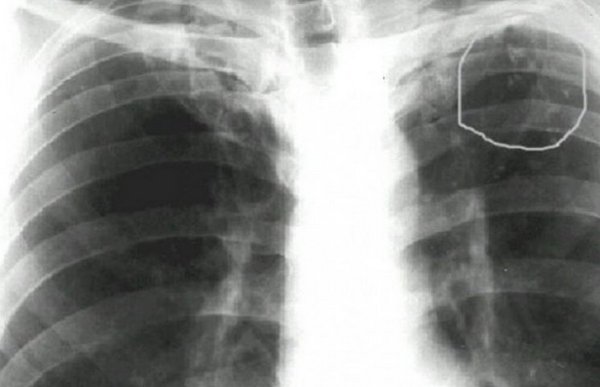

Метатуберкулезные изменения в легких возникают в результате замещения органа соединительной тканью. Часто они не имеют клинических симптомов и поэтому обнаруживаются при рентгенологическом исследовании. Чтобы выяснить причину изменений, необходимо пройти обследование у фтизиатра, после чего специалист подберет соответствующую тактику лечения, чтобы не допустить развития дыхательной недостаточности.

Метатуберкулезные изменения — это результат развития различных патологических процессов в легких. В большинстве случаев они связаны с перенесенным туберкулезом. Поэтому при обнаружении таких изменений на рентгенограмме или флюорограмме необходимо обратиться к фитозиатру, а затем провести дополнительные анализы.

• Кальцификаты — это множественные или одиночные отложения солей кальция, которые появляются в месте вспышки туберкулеза. Они почти не влияют на функциональное состояние легких, но способствуют снижению защитных сил, поэтому люди, принимающие кальциферол, чаще болеют простудой с бронхитом.